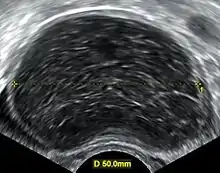

Image of multiple ovarian cysts.

A 2 cm left ovarian cyst as seen on ultrasound